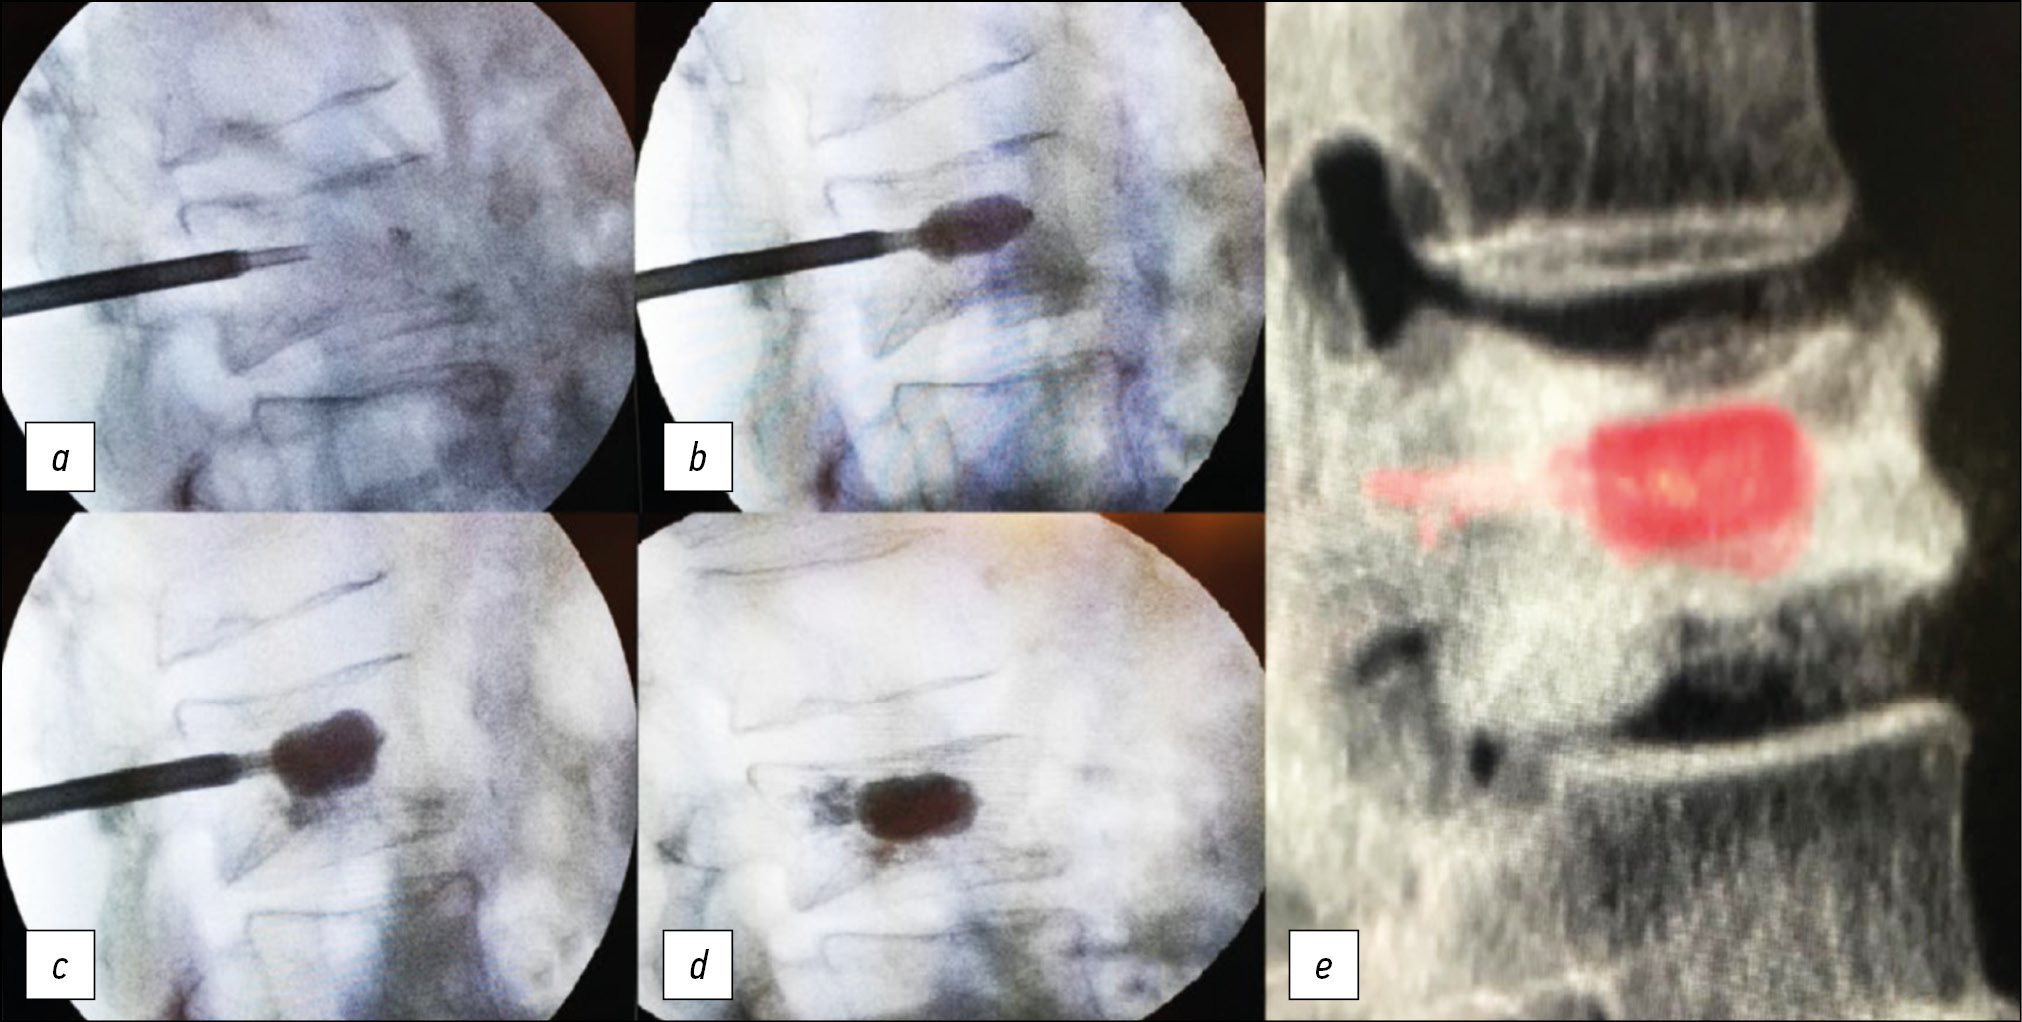

Technical success was defined as the correct placement and implant of the Vessel-X (Fig. 2).

Fig. 2. (a–d): Intraoperatory positioning of Vessel-X device. BMF starts to spread out of the PET container only after it reached its maximum size. (e): VR reconstruction of Vessel-X.